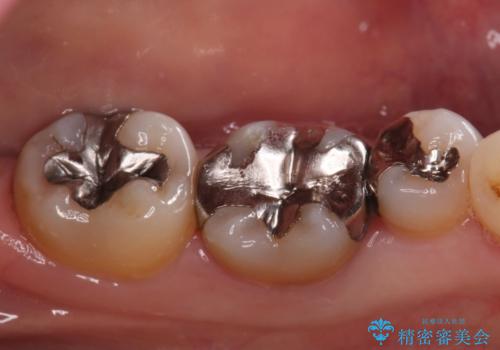

- ご友人との会話中などに、下の歯に入れてあるメタルインレーが見えてしまうのが気になり、やり変えを希望された患者様です。審美性、清掃性に優れたセラミックでの治療を希望されたため、セラミックインレー、クラウンで治療いたしました。